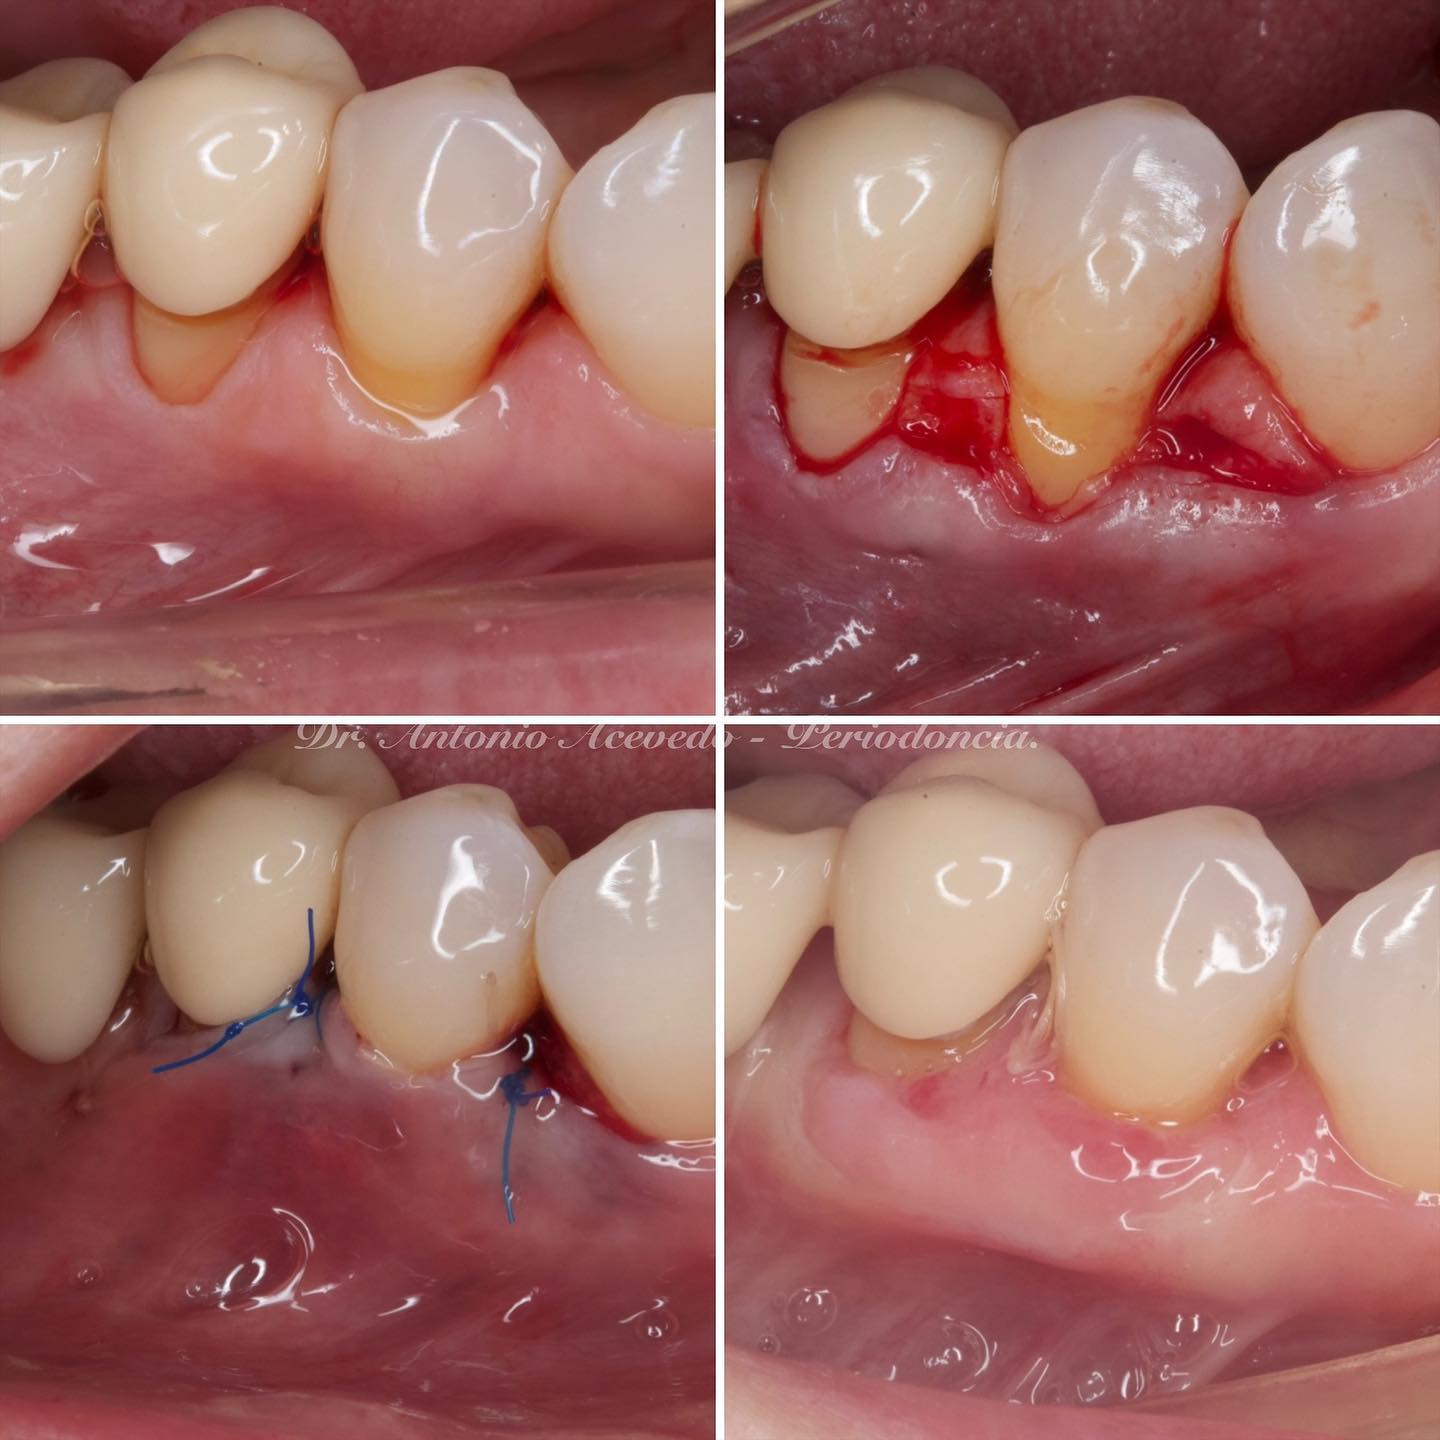

Durante una mañana, asistirás a una Cirugía Mucogingival de recubrimiento radicular de recesiones múltiples en IV y V sextante (36 a 43).

Gracias al uso del microscopio y a la proyección en tiempo real en pantalla, verás exactamente lo mismo que veo yo durante la cirugía, sin tener que estar

Podrás asistir a la planificación de casos y cirugía de injerto de tejido conectivo. Factores determinantes y elección de la técnica adecuada. Sumérgete en un protocolo predecible y técnicamente correcto para obtener resultados óptimos.

Aprende la planificación y técnica de la cirugía Mucogingival para el recubrimiento de recesiones y aumento de banda queratinizada en el sector anteroinferior

La formación comenzará con la presentación del caso clínico que se abordará durante el curso, seguida de una cirugía en directo, que permitirá observar paso a paso el procedimiento y la toma de decisiones clínicas. Durante la jornada se profundizará en los conceptos biológicos aplicados a

Una estancia clínica pensada para quienes quieran iniciarse o dar un paso más en el campo de la cirugía mucogingival. Durante esta experiencia tendrás la oportunidad de aprender en directo cómo se planifica y se lleva a cabo una cirugía mucogingival mediante técnica de Túnel.

Formación teórico-práctica completa sobre las técnicas más avanzadas en cirugía mucogingival. Durante dos días intensivos, los participantes aprenderán desde la evidencia científica y la anatomía de las zonas donantes hasta la ejecución de injertos, cubrimiento radicular y aumento de